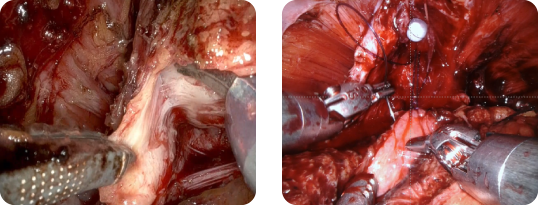

欧米を中心に導入され、近年ではアジア地域においても確実に普及されている手術用ロボット。日本においては、平成21年11月に薬事承認され、平成24年4月より、前立腺癌の手術につき保険承認されました。その手術ロボット「ダヴィンチ」が2012年4月、当院に導入されました。

初期の前立腺癌の治療法として開腹・腹腔鏡手術や放射線療法・内分泌療法などがあり、年齢・癌細胞の種類や他に患っている病気の有無により治療法が決定されています。

手術は最も根治性の高い治療ですが、一方で「尿失禁」や「性機能低下」の恐れが指摘されておりました。この手術ロボットは上記の問題を改善できるとされる最新鋭ロボットです。出血量を少なく、小さい傷で痛みが少ないため、尿失禁や勃起障害などの合併症を軽減できるとされています。

前立腺は、骨盤の一番奥深く狭い空間に位置します。また、周囲には尿失禁を防ぐ筋肉をはじめ勃起に必要な神経や血管が密集している為、周囲組織を傷つけず前立腺を摘出することは至難の業です。このような狭い場所での手術に適する機械が手術ロボット「ダヴィンチ」です。あらゆる方向に屈曲可能な器具を有するので、これまで以上に高度な手術が可能となります。

ダヴィンチは手術操作のアーム(patient cart)【図1】と医師が操作するメインの機械(surgeon console)【図2】と工学系を統合するvision system【図3】より構成されます。あたかも開放手術のような距離感のある3D映像をみながら操作するアーム。そのアームはあらゆる方向に屈曲可能な関節を有する器具であり、人の手の数倍の細かさで動かすことができます。また、手の震えを吸収する機能も備え、腹腔鏡手術と比較し、安全性・操作性において高い評価があります。